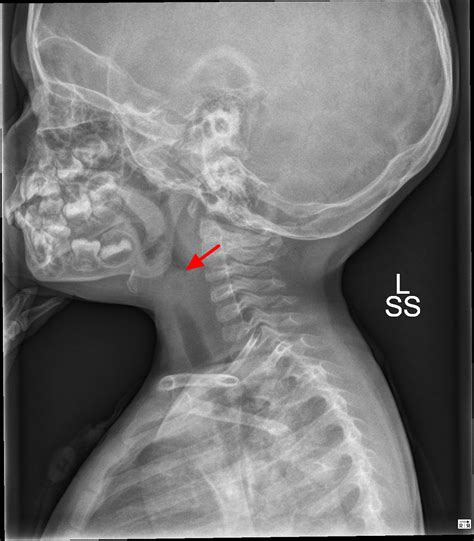

Radiological Identification: The Thumbprint Sign

The Thumbprint Sign Epiglottitis is observed on a lateral soft tissue neck X-ray. Under normal conditions, the epiglottis appears as a thin, wispy shadow. In cases of acute epiglottitis, the inflamed tissue projects posteriorly and superiorly, creating a rounded, dense, soft-tissue opacity that resembles the distal phalanx of a human thumb. Hence, it is commonly called the "thumbprint sign."

However, when the epiglottis becomes infected—typically by Haemophilus influenzae type b (Hib) in unvaccinated populations or other pathogens like Streptococcus pneumoniae—it becomes severely inflamed and edematous. This swelling causes the structure to thicken and enlarge, which is what radiologists identify as the Thumbprint Sign Epiglottitis. Because the airway space is limited in the pharyngeal region, this rapid swelling can quickly lead to complete airway obstruction, making prompt recognition vital.